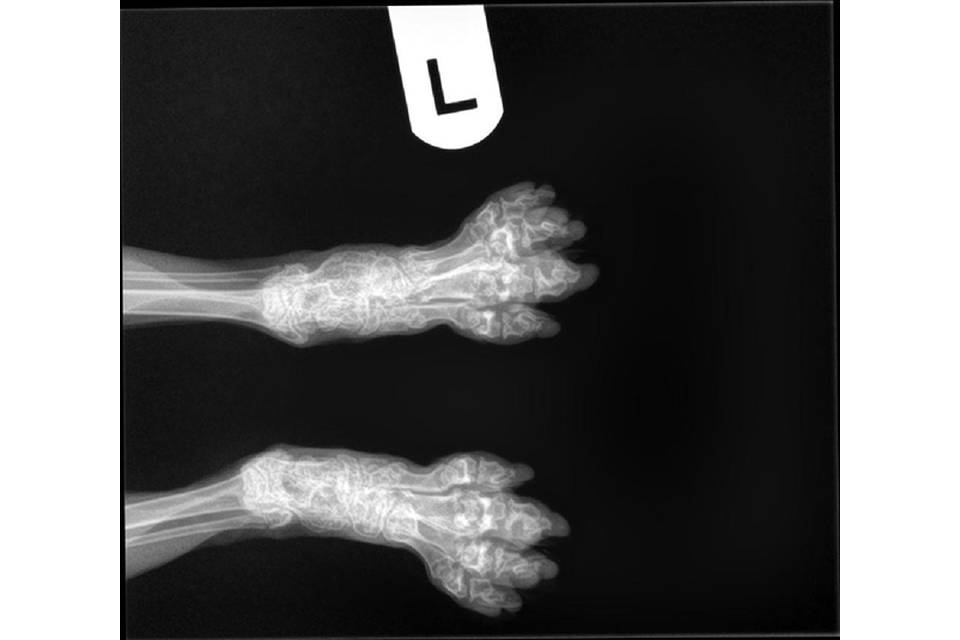

SFO is een erfelijke aandoening die voorkomt bij de Scottish Fold. Door deze afwijking zal het kraakbeen niet normaal volgroeien en functioneren. Hierdoor ontstaat ernstige artrose. Dit kan al op jonge leeftijd zichtbaar zijn en leidt ertoe dat aangetaste dieren mank en stijf gaan lopen en minder of niet willen springen.

De diagnose kan bevestigd worden door het maken van röntgenfoto's.